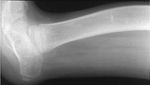

Selama proses ini, lutut dan pergelangan kaki ditopang dengan brace engsel agar tidak terjadi kelainan bentuk. Pasien juga mengikuti fisioterapi intensif agar sendi tetap lentur dan otot tidak melemah. (Foto: The Journal of Bone & Joint Surgery)

Setelah tulang baru mengeras, alat dilepas dan kaki dilindungi dengan penyangga eksternal khusus dari paha sampai telapak kaki selama hingga 2 tahun untuk membantu menjaga keseimbangan. (Foto: The Journal of Bone & Joint Surgery)